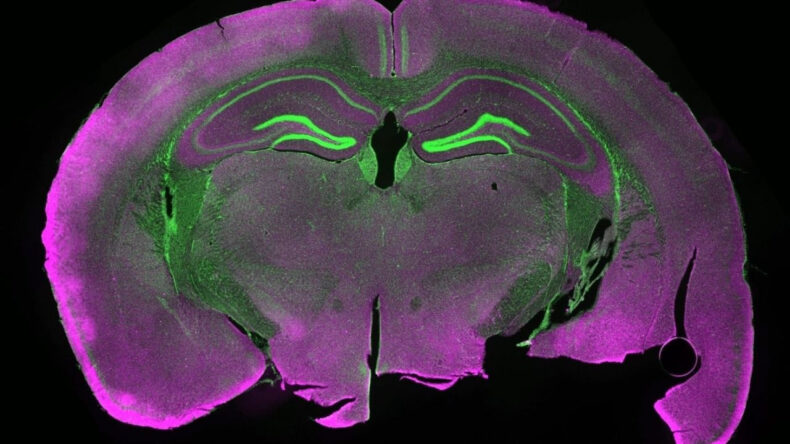

Daha sonra da fare beyninden alınan hipokampüs dilimleri sıvı nitrojende -196 dereceye kadar soğutuldu. Doku tekrar ısıtılırken hücrelerin şişmesini ve çatlamasını önlemek için ise özel bir kimyasal “antifriz” solüsyonu kullanıldı.

Mikroskop altında yapılan incelemelerde nöronlar arasındaki sinaptik bağlantıların büyük ölçüde korunduğu, hücrelerin enerji üretim merkezi olan mitokondrilerin yeniden aktifleştiği, elektriksel uyarı verilen nöronların ise tekrar sinyal üretebildiği saptandı.